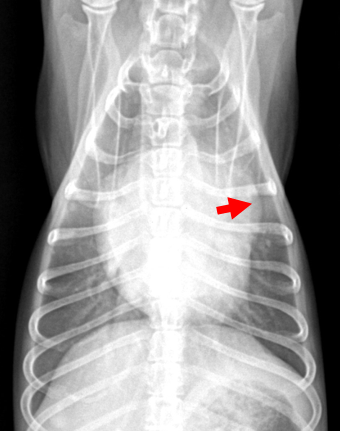

| 2기 (Moderate) |

| 기존 소견 동일하게, 1) 심장 커짐 Left auricle 확장, cranial/caudal waist 소실, Globoid heart, Cardiomegaly + Sternal contact 매우 증가 2) 기관 영향 Tracheal elevation, bronchus compression ⇒ Static collapse로 발전 3) 판막, 역류, 심잡음 판막의 thickening (glycose aminoglycan 침착) = Myxomatous degeneration = mitral valve prolapse (MVP, 판막이 뒤로 휨) ⇒ Regurgitation, systolic murmur (심잡음 6단계 중 3단계) 4) 기절 기침 증상이 심하면 syncope (산소 포화도와 혈압이 감소하면서 cardiac output이 감소했기 때문) + interstitial pattern, LA rupture 가능성, 너무 늘어나니 수축이 잘 안 되어 심방부정맥. |